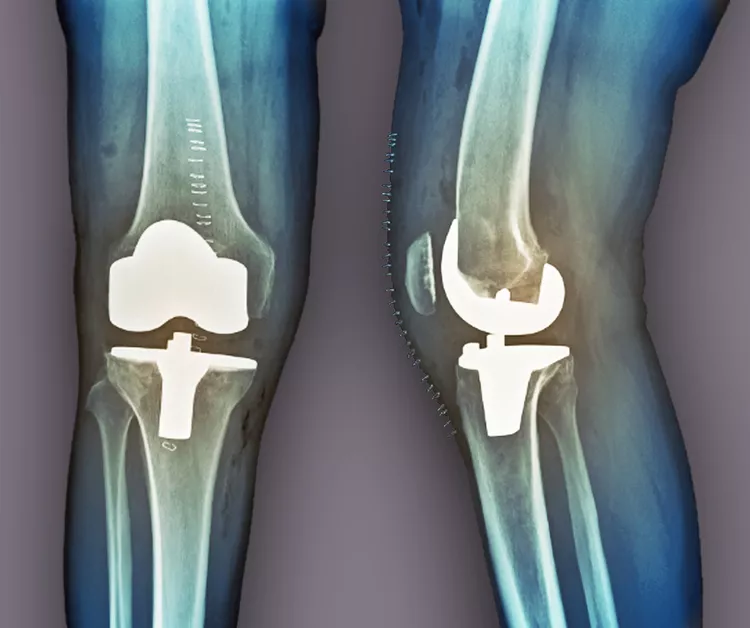

當(dāng)其他療法失敗時(shí),關(guān)節(jié)置換術(shù)是最后選擇。在這種手術(shù)中,醫(yī)生會(huì)切除膝蓋受損部位,并用金屬或塑料部件代替。如果這種方法不起作用,通過融合連接骨頭可能會(huì)緩解疼痛。缺點(diǎn)是,在這種手術(shù)后,其他關(guān)節(jié)最終會(huì)承受更大的壓力,以補(bǔ)償融合關(guān)節(jié)的運(yùn)動(dòng)損失。